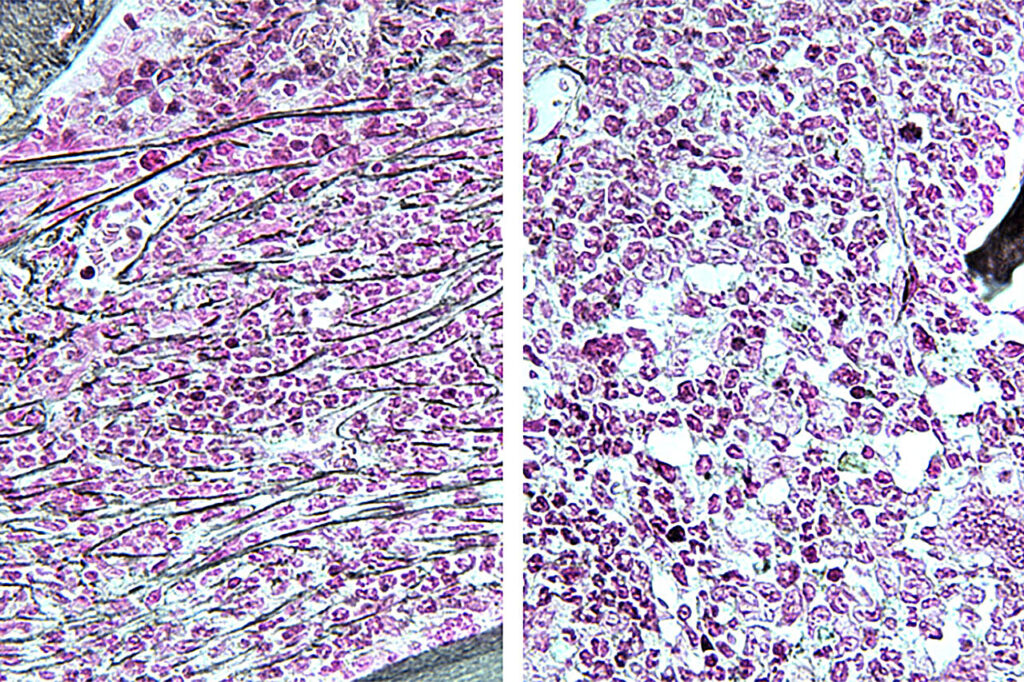

Highly invasive tumor hijacks neurons to grow, but a common heart medication offers hope

Chinese researchers have revealed new insights into the growth of craniopharyngioma and identified a potential therapeutic treatment. Their findings are published online in Science Translational Medicine.